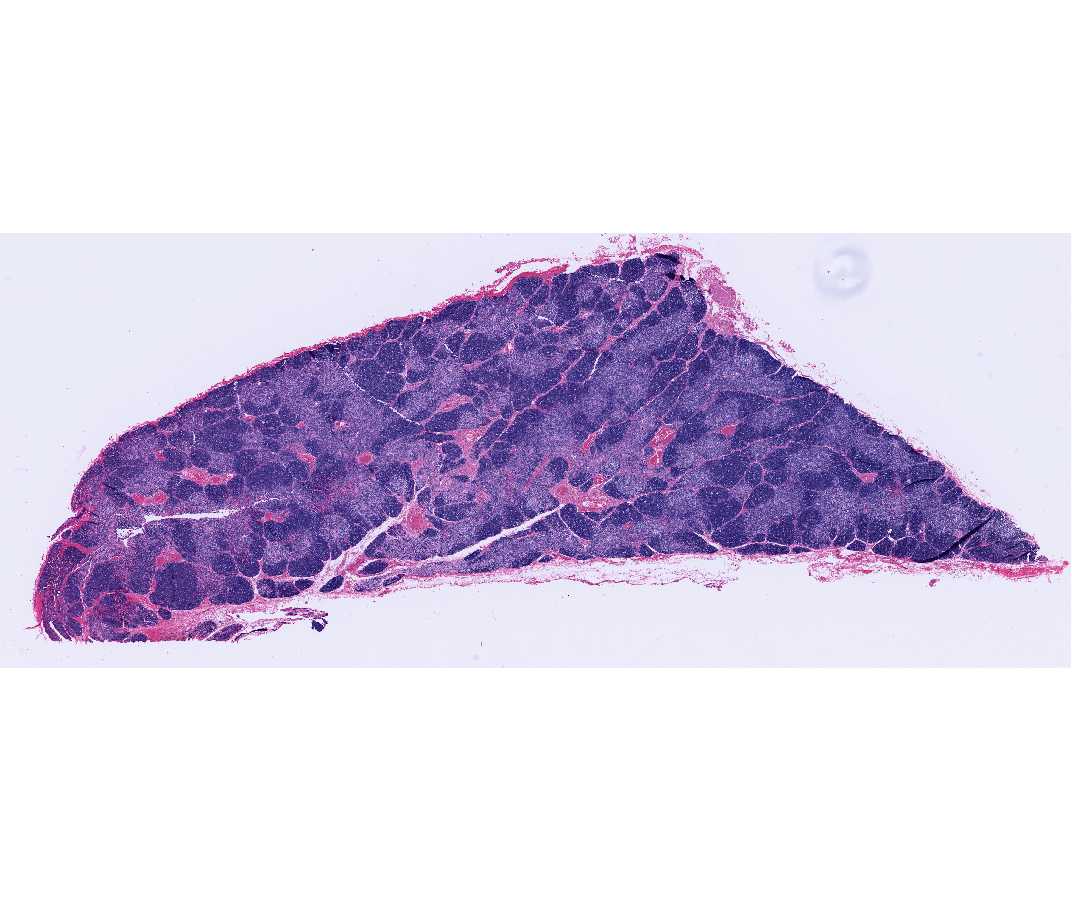

Histology Laboratory Manual

www.columbia.edu

www.columbia.edu

histology spleen thymus slide columbia rabbit laboratory manual webviewer open itc sbpm hs medical edu